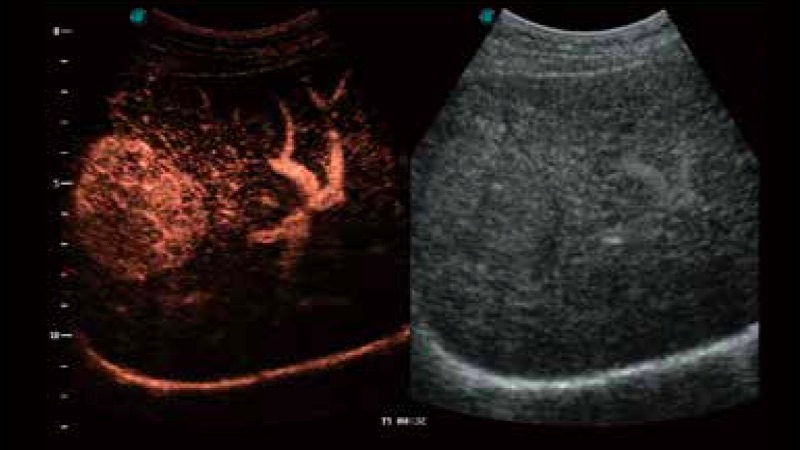

SR Flow高分辨率血流成像

高分辨率血流成像技术提高了对低速血流信号的检测能力。在提高空间分辨率的同时,也克服了血流外溢现象,为用户提供更加真实的血流动力学信息。

造影成像

造影成像功能和定量分析工具包使医生能够更好的评估血流灌注情况。独特的动态声压控技术有效控制造影剂的声压,保证更长的造影剂持续时间,更好的观察病变灌注的延迟相位。

S-Live 高分辨率容积成像

通过仿真成像技术对3D/4D立体数据进行渲染,多种初始光源位置可选,并支持轨迹球360°光源位置自由调节,清晰显示不同方位容积图像细节。